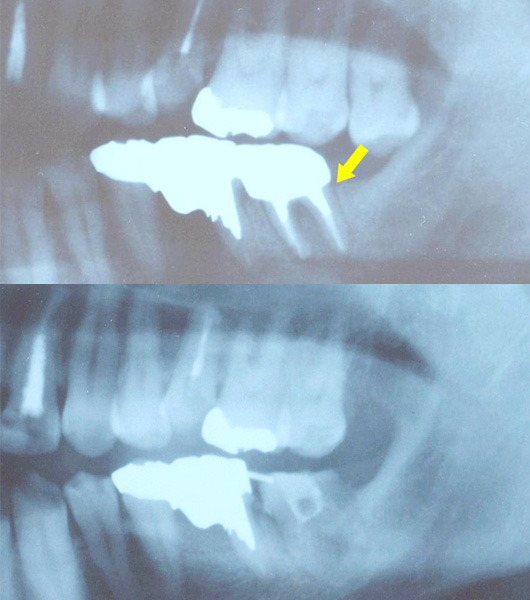

1ヶ月前から右下奥歯が噛むと痛く歯茎も腫れ、抜歯と診断されたとのことで来院されました。

金属の土台が入っていた根元から歯根破折しており、接着修復を行いました。

痛みや腫れ、深いポケットも消失し、その後も問題なく機能しております。